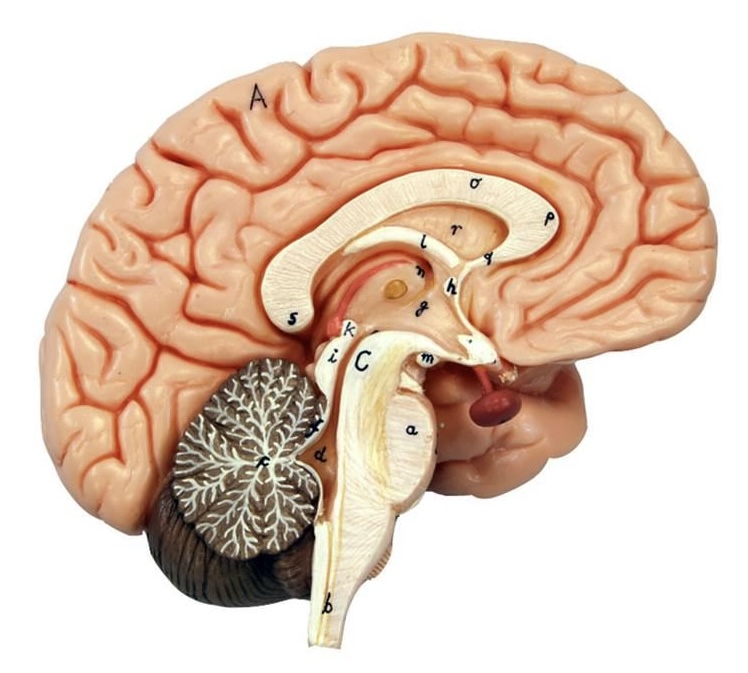

What is D?

lateral ventricle

Imagine thin membrane separating the 2 lateral ventricles

septum pellucidum

What is C?

3rd ventricle

What is B?

cerebral aqueduct

What is A?

4th ventricle

What is below A at the very end?

central canal (spinal cord)

What is C?

midbrain

tectum (corpora quadrigemina): superior colliculus

tectum (corpora quadrigemina): inferior colliculus

What is a?

pons

medulla oblongata

intermediate mass of thalamus

hypothalamus

What is the pink bulb?

pineal gland

corpus callosum

fornix

What is A?

cerebral cortex

cerebral tracts

cerebral hemispheres

longitudinal fissure

What are these ridges?

gyri

What are these shallow grooves?

sulci

Divides parietal from frontal lobe

central sulcus

precentral gyrus

postcentral gyrus